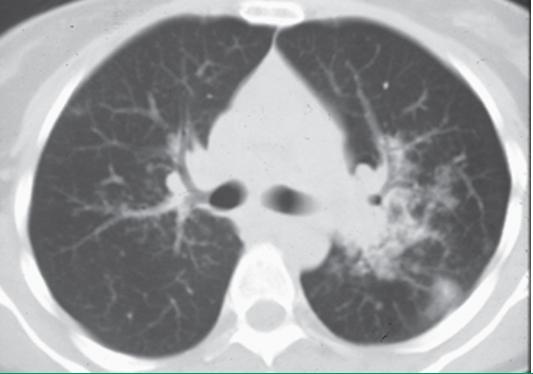

常规行胸部HRCT以评估胸片所见异常;或者评估胸片正常,但原因不明的呼吸困难或咳嗽。HRCT可发现胸部X线平片未能发现的肺实质和纵隔异常。HRCT扫描通常显示肺实质变化主要分布于中上肺野:

- 肺门和纵隔淋巴结肿大

- 支气管血管束串珠样增厚或不规则增厚

- 沿支气管、血管及胸膜下区域分布的结节

- 支气管壁增厚

- 磨玻璃样不透明影

- 肺实质肿块或结节性实变,偶伴有空洞

- 肺实质条索

- 囊腔

- 纤维化伴肺结构变形和牵引性支气管扩张

实际上HRCT检查还可以协助医生与其他疾病鉴别。

左肺门周围大而不清楚的实变,单侧左肺门扩大,双侧周围结节不清楚